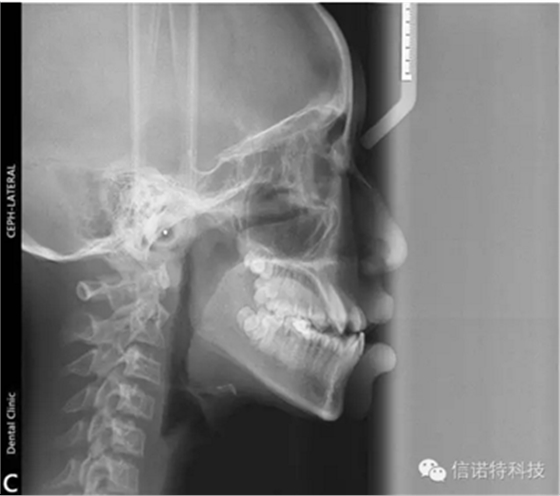

常用X線頭影測(cè)量的標(biāo)志點(diǎn)

節(jié)選自《口腔正畸學(xué)》主編:傅民魁 林久祥

這些標(biāo)志點(diǎn)中,有些是在正中矢狀面上,是單個(gè)的點(diǎn)。如鼻根點(diǎn)、蝶鞍點(diǎn)等。而有些則是雙側(cè)的點(diǎn),如下頜角點(diǎn),關(guān)節(jié)點(diǎn)等。若由于面部不對(duì)稱而使兩側(cè)之點(diǎn)不重疊時(shí),則取二點(diǎn)間的中點(diǎn)作為校正的位置。